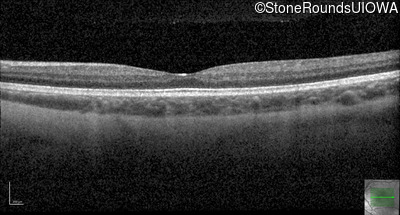

Optical Coherence Tomography - Left - 20/40

Exemplar / OCT Stack